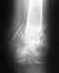

Мне 28 лет. Был закрытый осколочный перелом левой плечевой кости в двух местах. Установили титановый штифт. Спустя 10 месяцев, во время тренировки - штифт сломался. Легла в больницу - поставили диагноз ложный сустав, в чём я сомневаюсь, ведь на протяжении 10 месяцев ничего не беспокоило. Сейчас хотят проводить костную пластику - срезать кость в другом месте и вживлять в руку + скреплять титановой пластиной или накладывать Илизарова. Есть ряд впросов:1.Есть ли более щадящие методы лечения? 2.Поможет ли вместо Илизарова - обычный гипс?3.Действительно ли это ложный сустав?4.Можно ли жить с ложным суставом?Вот мои ренгеновские снимки: http://comp.sky.ru/temp/img556.jpghttp://comp.sky.ru/temp/img557.jpg

Беспокоило или не беспокоило Вас что-то в предыдущие 10 мес. - уже не важно, на сегодня очевидно, что конструкция разрушена, а сращения нет.

Как назвать эту ситуацию - несращение, ложный сустав - непринципиально.

Варианты лечения возможны все: и накостный остеосинтез с костной пластикой, и остеосинтез по Илизарову, и замена на другой штифт. Гипсовая повязка скорее приведет к потере движений в локтевом суставе, чем к сращению.

Спасибо Вам ! А почему держится температура? 37,2 в среднем. Уже месяц. Как при переломе. Нет ли там на рентгене признаков остиомиелита?